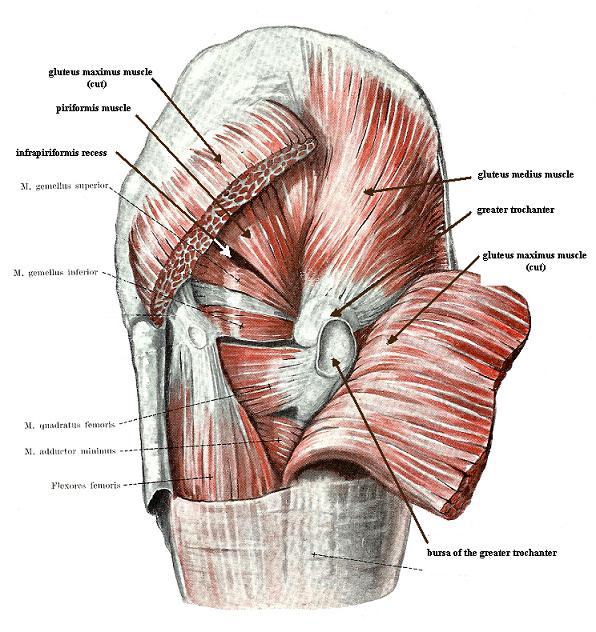

Анатомия мышц: Пириформис